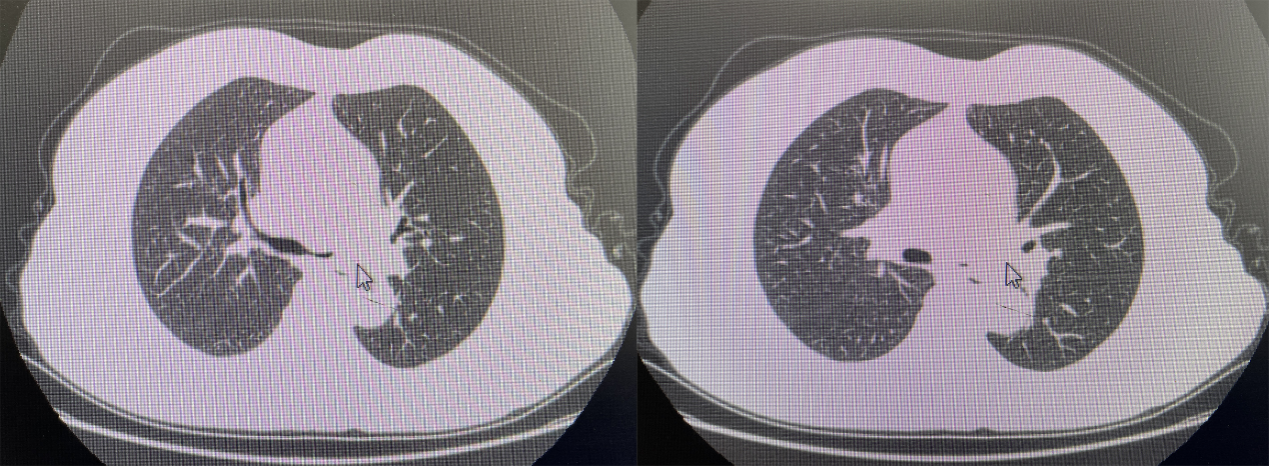

患者张某,女 ,63岁,因“反复咳嗽2年”入院,患者院外反复吃药、输液等治疗后均未见好转,故到来凤县中心医院呼吸内科就诊。入院后查血常规、肝肾功能、凝血功能、CRP、PCT、心电图、肺炎支衣原体、痰培养、痰抗酸染色均未见明显异常。胸部CT提示如下:

左侧主支气管壁增厚,腔内片状高密度影。病变性质不明确,究竟是肿瘤、感染性病变还是异物引起?为明确诊断,我们给她做了支气管镜检查,镜下见左主支气管前侧大量白色干酪样坏死物,管腔狭窄,管腔黏膜有糜烂溃疡面。